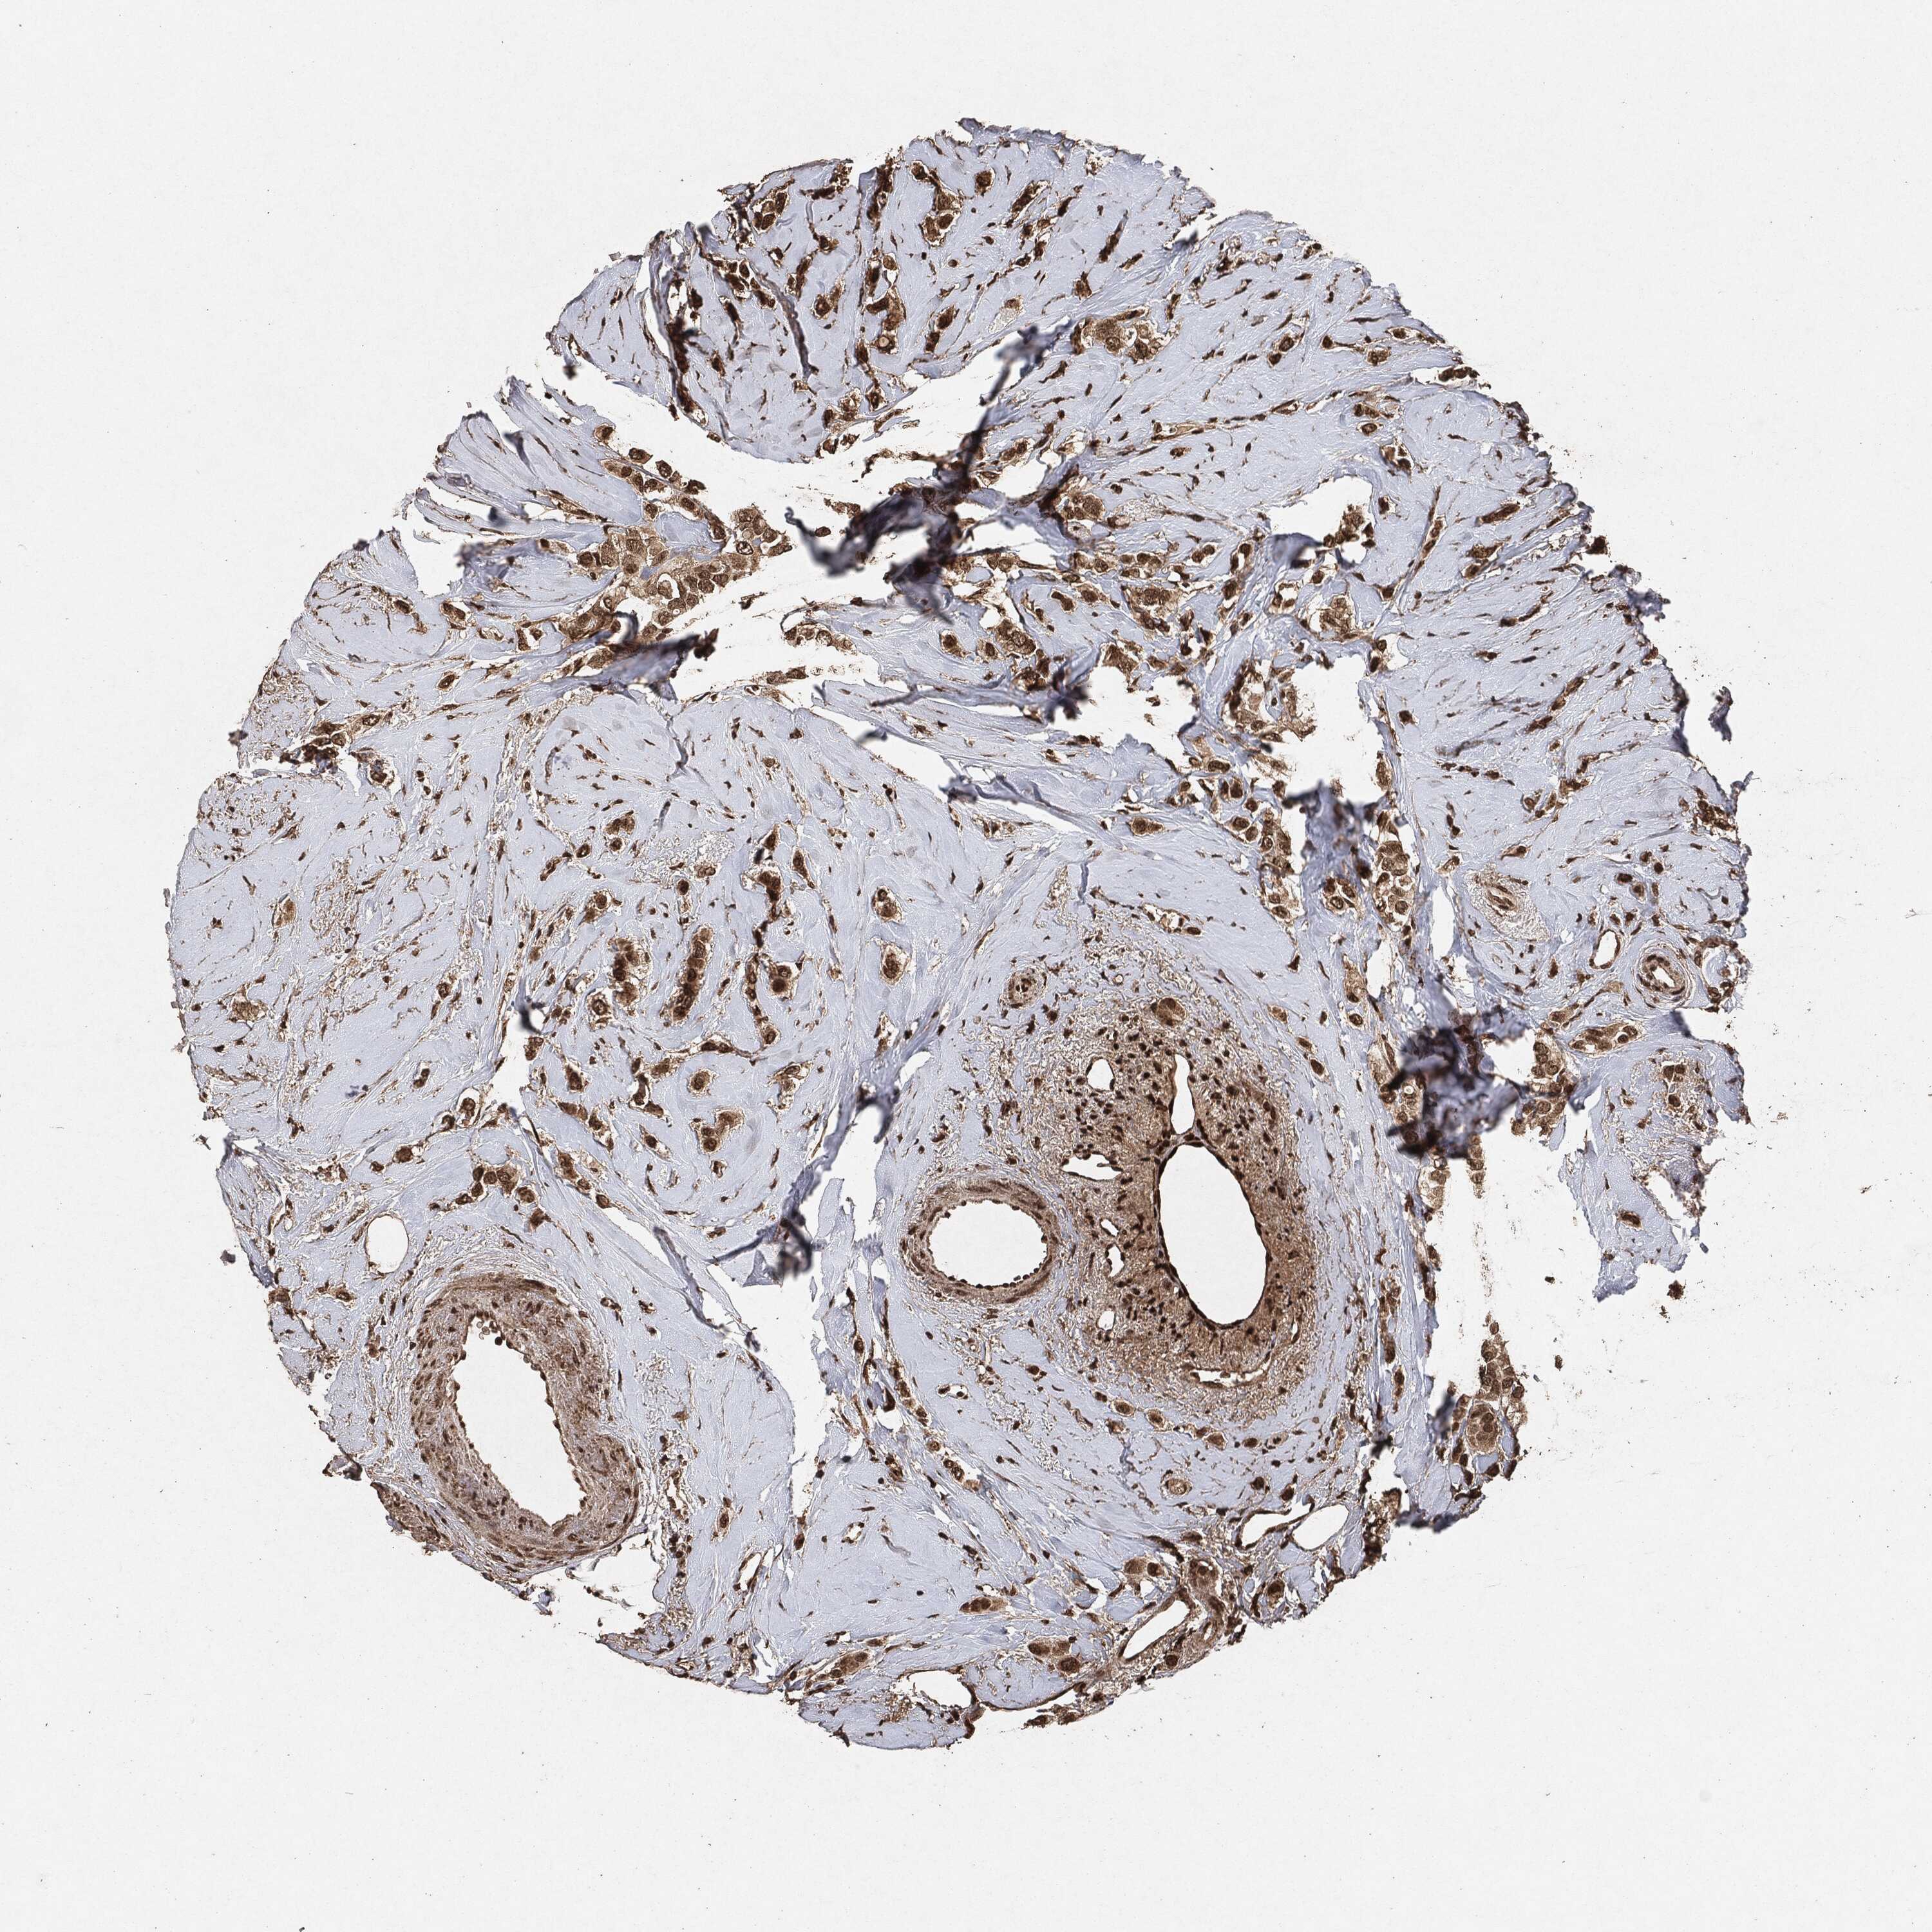

CANCER BREAST CANCER Show tissue menu

BRCA TCGA BRCA VALIDATION PROTEIN EXPRESSION

ANTIBODIES

AND

VALIDATION